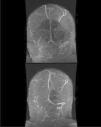

El día 11.° del ingreso se realiza ventana de sedación, presentado la paciente apertura ocular espontánea con disfasia motora leve y hemiparesia derecha de predominio braquial. En una TAC craneal urgente con contraste se descubren defectos de repleción en los senos venosos sagital superior, recto, transverso y sigmoide izquierdos, en relación a la TVC, e infartos en región frontotemporal y hemisferio cerebeloso izquierdos con áreas hemorrágicas. Se inicia tratamiento con heparina de bajo peso molecular y se completa estudio con RM craneal y angio-RM venosa cerebral que confirma el diagnóstico (figs. 1 y 2). En el estudio de hipercoagulabilidad destaca una determinación de anticoagulante lúpico positiva. Dada la presencia de componente hemorrágico en el infarto cerebral y la evidencia disponible8, se decidió continuar tratamiento anticoagulante con dabigatrán. En las semanas posteriores en planta presenta una evolución lentamente progresiva con estabilidad respiratoria, iniciándose tratamiento rehabilitador con tendencia a la mejoría de la hemiparesia y recanalización parcial de la TVC con control de la RM a los 2 meses, sin otras complicaciones.

Angio-RM cerebral que muestra trombosis venosa extensa, que afecta a senos longitudinal superior, transverso y sigmoide de ambos hemisferios (A). Control en un mes (B) con recanalización parcial del seno longitudinal superior, transverso y sigmoide izquierdos tras tratamiento con dabigatrán.